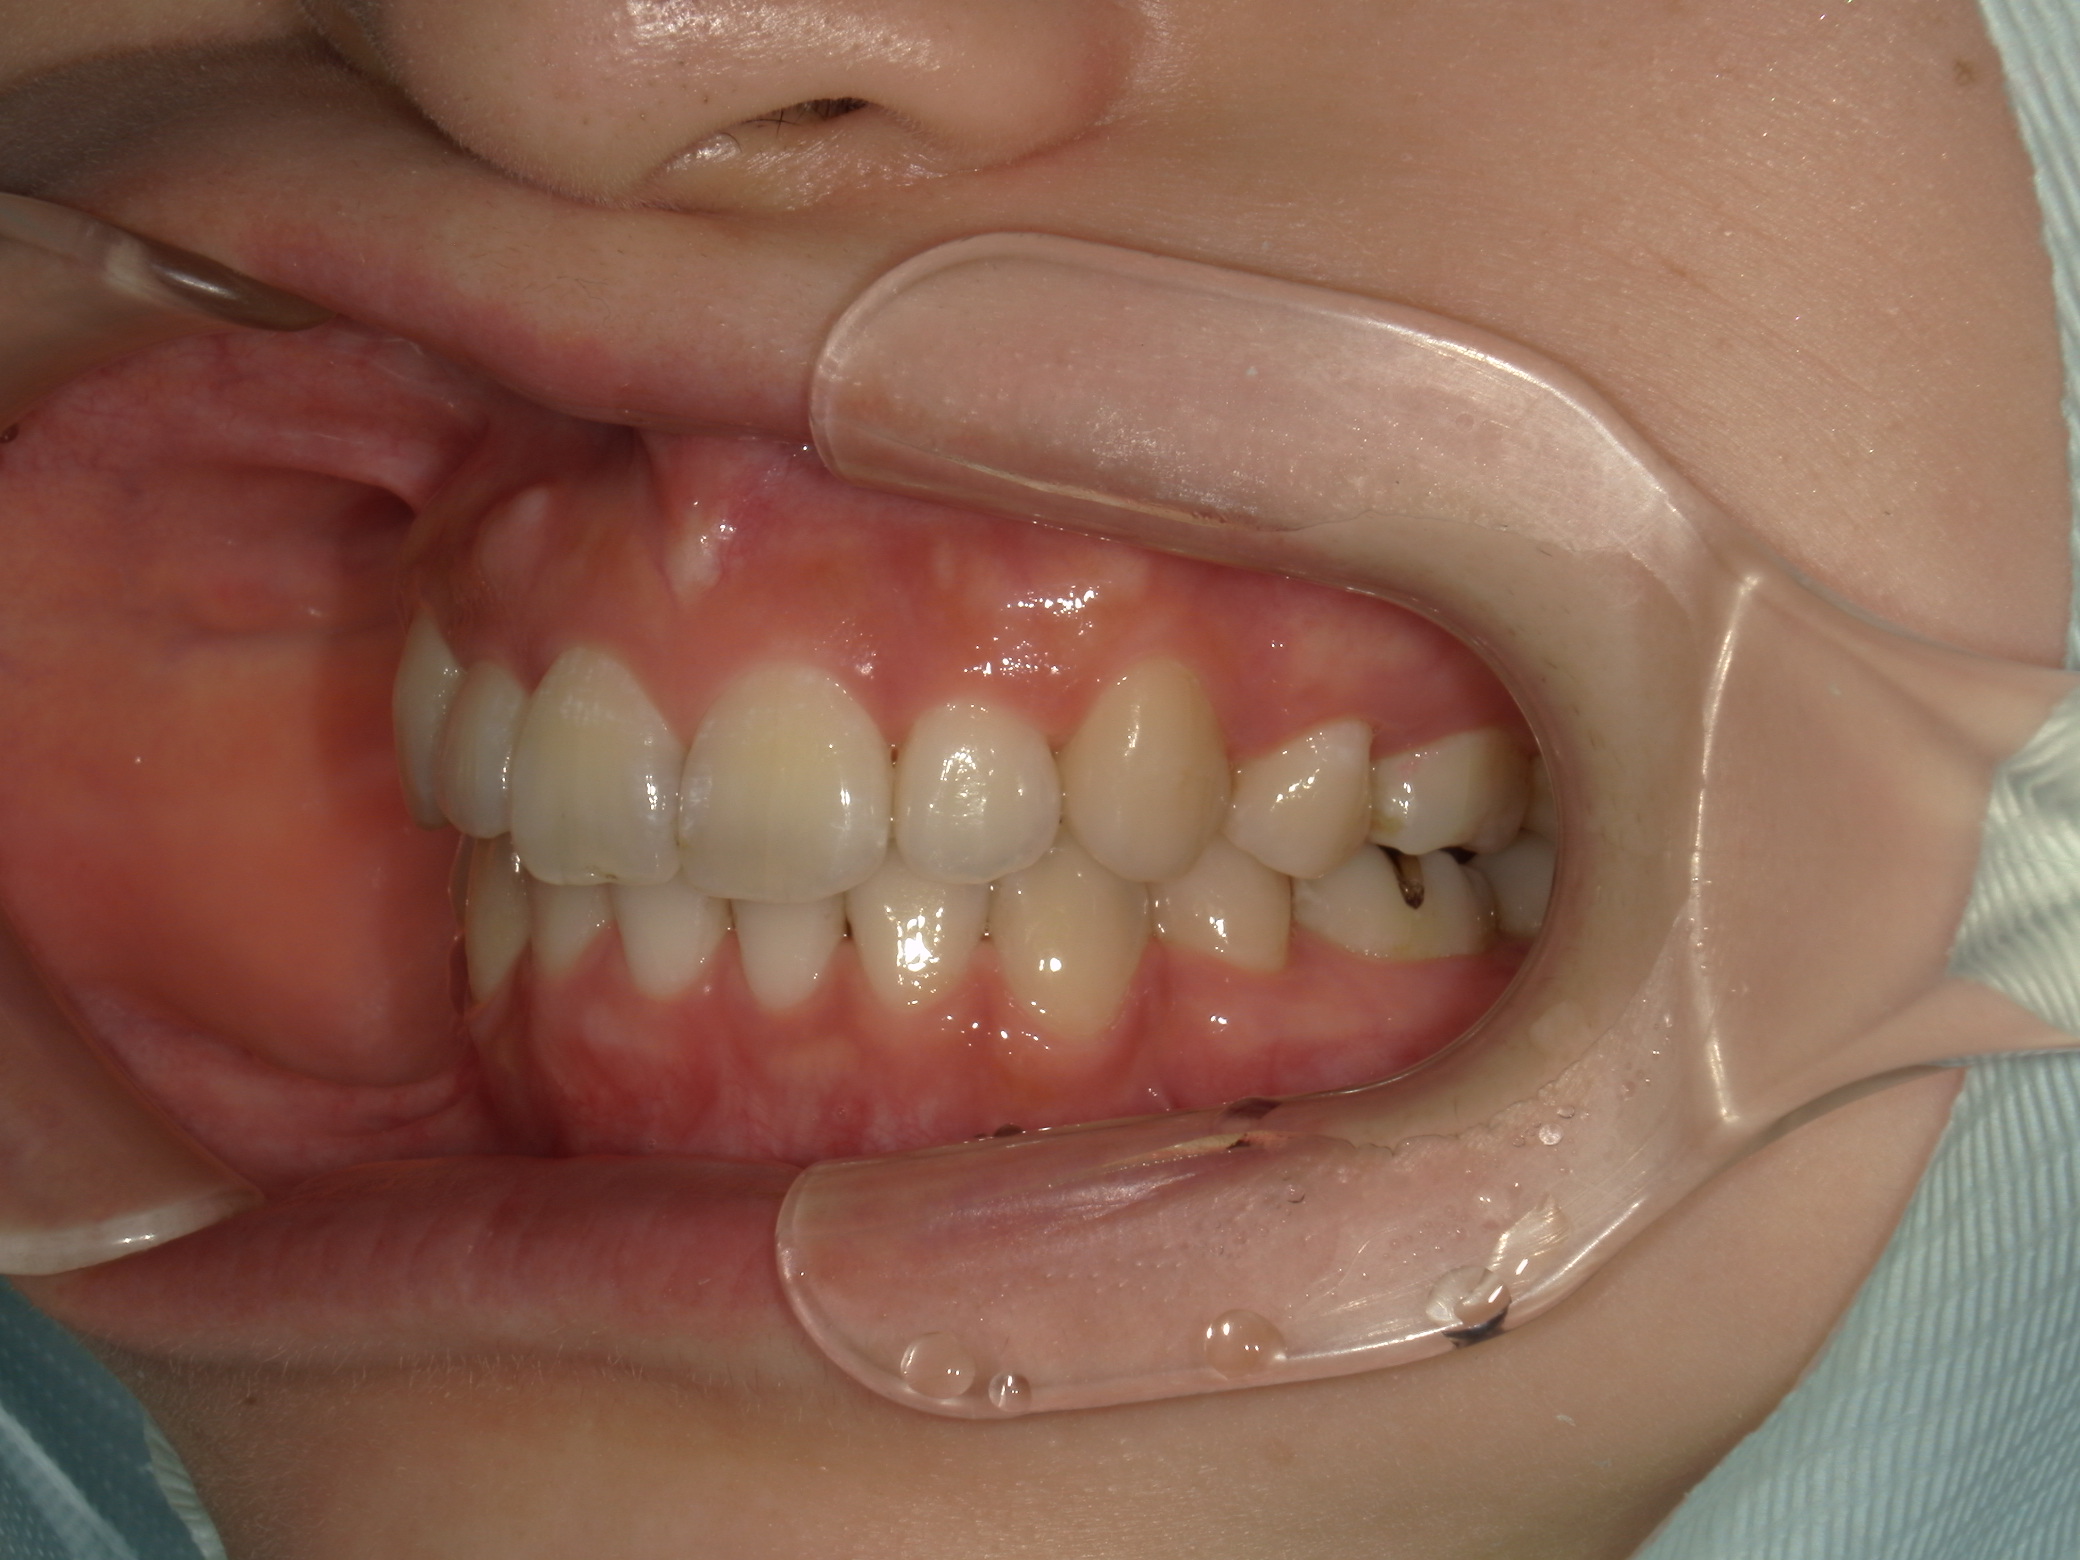

歯並びのガタガタ

上下顎に叢生(歯並びのガタガタ) と部分的な反対咬合を認める。

本症例は上下小臼歯抜歯により叢生解消のスペースを獲得し、下顎位の後退があることからダイレクトスプリント治療を併用して顎位の安定を求めた。